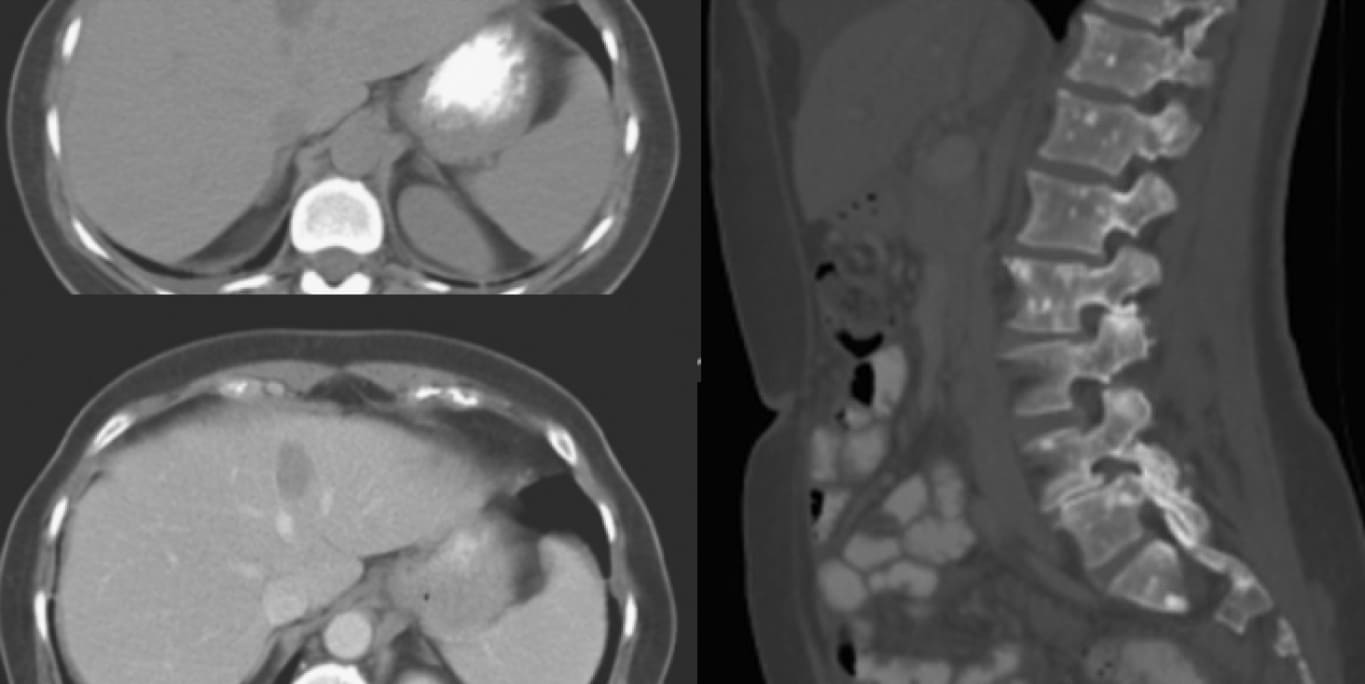

По данным компьютерной томографии выявлено опухолевое поражение головного мозга:

Рис. 1 — срезы компьютерной томографии головного мозга с внутривенным контрастированием. Отмечается наличие опухолевого очага в правой височной доли с признаками перитуморального оттека и нарушения ликвородинамики

Назначено дообследование. По МСКТ органов грудной клетки, брюшной полости и малого таза с внутривенным контрастированием вы констатируете наличие еще и экстракраниальных очагов поражения в костях и печени.